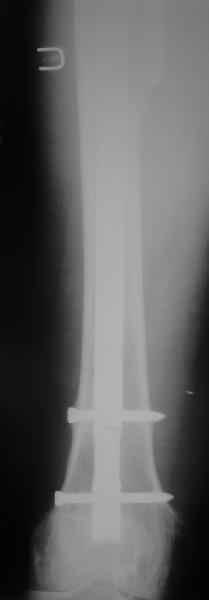

Произведено закрытое удлинение ножки эндопротеза с помощью ретроградного интрамедуллярного стержня. Продолжительность операции 3 часа. Два из них закрытое восстановление длины бедра диистрактором

А нельзя ли увидеть и профиль бедра на всем протяжении, т.е. и весь протез, и весь стержень? И фас бы с коленом.

новые снимки

Пациента удалось осмотреть недавно. Достигнутый результат сохраняется. Перелом бедра сросся. Конечность опорная и безболезненная, ходит без трости. Ножка, похоже, реинтегрировалась, как и надеялись. Снимки и фото в приложении. Комментарии приветствуются.

Надо ли что-то делать дальше, как полагаете? Убрать винты? Убрать "удлинитель ножки"? Или оставить все, как есть? Спасибо заранее.